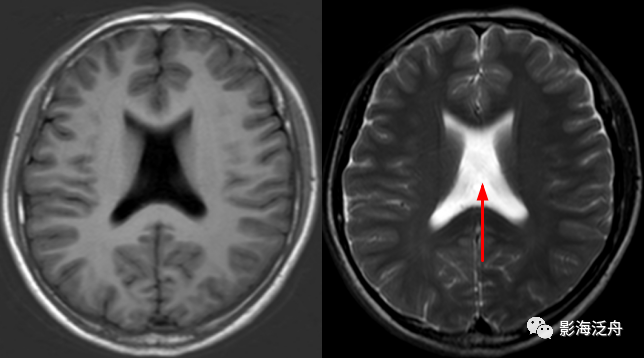

透明隔缺如,我自己漏诊过的病例。上面有很多正常的图像可供对比观察。